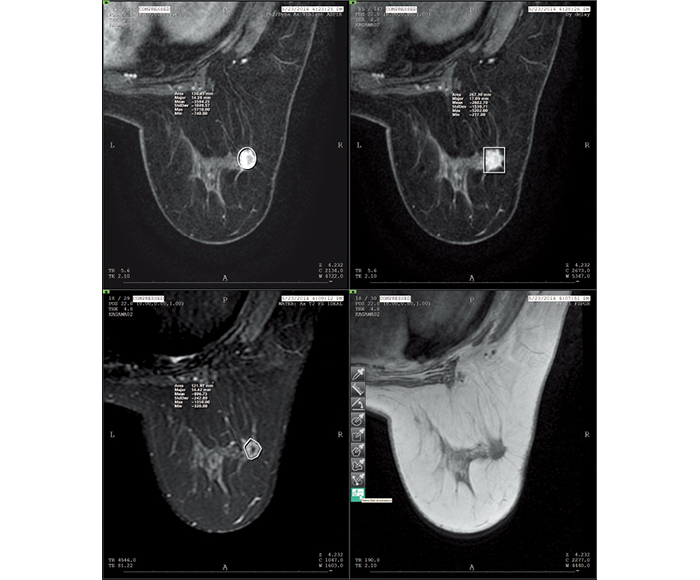

Values for ROI and X-ray gauging can be obtained from the information in each imaging modality.

![[image] ROI (Region of interest) X-ray](https://asset.fujifilm.com/www/ar/files/2025-07/046bfe4bfc03d6ebc9e27f55b5106b78/pic_amulet-bellus-2_05.jpg)

ROI (Region of interest)

![[image] Time intensity curve X-rays](https://asset.fujifilm.com/www/ar/files/2025-07/3f4b2c212d2a9ccf77989eac7a2e1f6d/pic_amulet-bellus-2_06.jpg)

Time intensity curve

![[image] Scale](https://asset.fujifilm.com/www/ar/files/2025-07/930ee34d33876de1a6cddf0c65159250/pic_amulet-bellus-2_07.jpg)

Scale